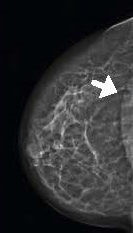

Planmed Clarity™2D – передовая система цифровой визуализации для скрининга и маммографической диагностики. Аппарат максимальным образом оптимизирован для обнаружения рака молочных желёз на ранней стадии. Оборудование легко трансформируется из системы с 2D проекцией в высокоэффективную диагностическую систему с функцией томосинтеза (опционально).

- максимальный обзор тканей груди во всех традиционных проекциях маммографии благодаря запатентованной системе MaxView™;

- чёткое представление на мониторах тончайших тканей и микрокальцификаций благодаря технологии Continuous-Sync-and-Shoot™;